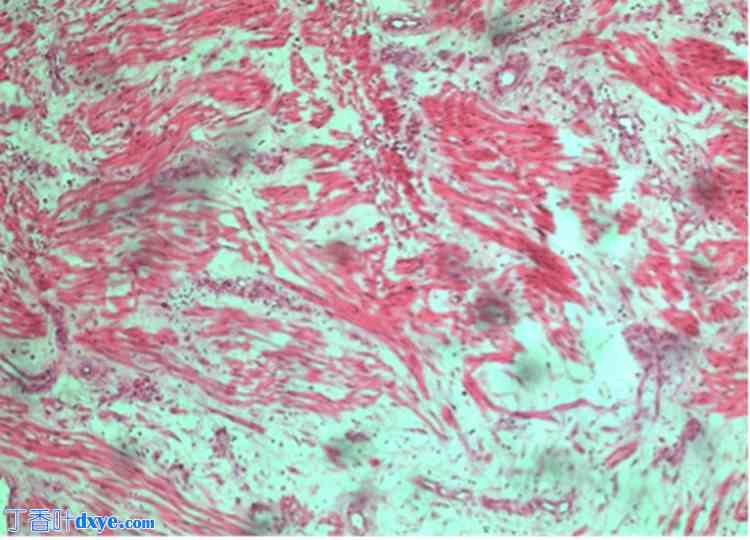

患者接受了剖腹探查术。术中,作者发现一个直径10厘米的大肿块起源于腹膜后,并粘附于子宫后壁。同时,还有两个较小的肿块,约2-4厘米,附着于子宫附近的左腹膜壁层(图2)。此外,还可见正常的子宫、双侧输卵管和卵巢。作者切除了所有三个肿块,没有损伤肠道、血管、输尿管和膀胱。患者术后恢复良好,迄今为止无症状。图3显示肿瘤结构由梭形细胞组成,细胞核小而圆,与肌瘤结构相似。

图3. 肿瘤碎片由梭形细胞组成,细胞束交织排列。细胞核小、圆、大小均匀,无有丝分裂或坏死。可见囊性变和嗜酸性变性区域。未检测到异形细胞。